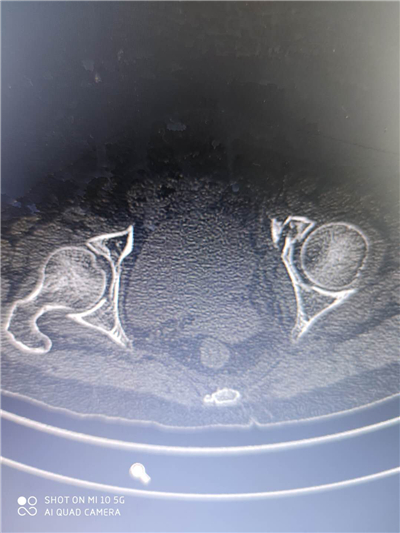

术前ct示:左侧髋臼骨折: